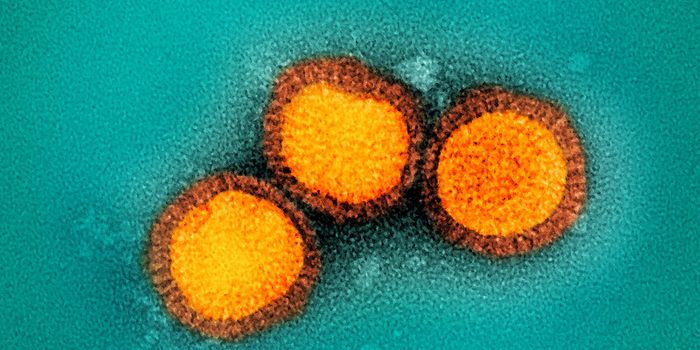

FEB 21, 2020Clinical & Molecular DXDiagnosing coronavirus is done through next-generation sequencing, real-time RT-PCR tests, cell culture, and electron mi ...